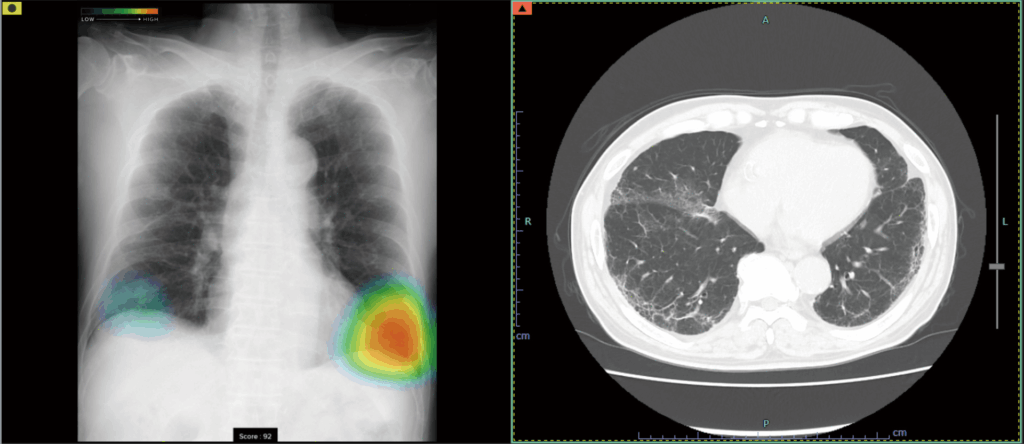

このシステムは、胸部レントゲン画像をAIが解析し、肺炎や結核、肺がんなどの異常の可能性を示す部位を検出して医師の診断をサポートするものです。

検出対象となるのは、主要な肺疾患に関連する「結節・腫瘤影」、「浸潤影」、および「気胸」の3つの画像所見です。

写真は「浸潤影」の画像。

◆ヒートマップ表示機能(画像の青~赤色の部分)

CXR-AIDが候補領域の解析をおこなったのち、0~100に応じた確信度が色分けされ表示されます。

◆スコア表示機能(左側写真の一番下にScoreと表示)

画像単位の解析結果として、画像内の確信度の最大値が数値で表示されます。